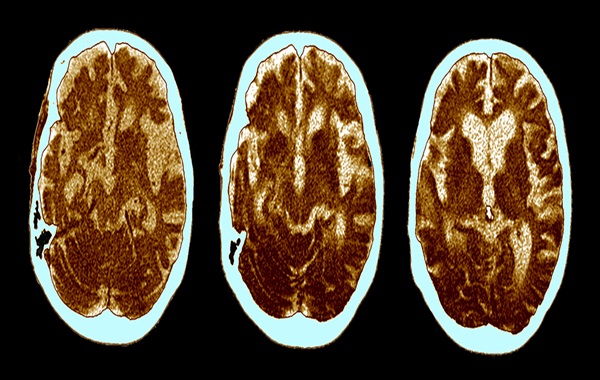

Alzheimer’s disease is commonly associated with clumps and tangles of proteins building up in brain cells. Yet for more than a century, accumulations of a completely different material have also been linked with the neurodegenerative condition.

A study led by researchers from the Stanford University School of Medicine returned to observations of large fat drops made by Alois Alzheimer when he made critical descriptions of the pathology at the turn of the 20th century.

Over the years, those lipid deposits haven’t received as much attention as other biological changes linked to Alzheimer’s – such as the bundles of amyloid beta and tau proteins in the brains of people with the disease. The new study was looking to change that.